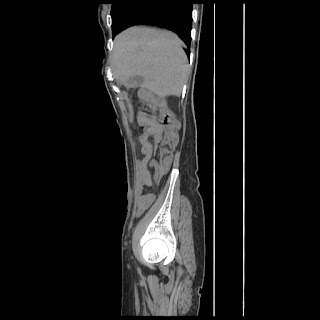

Radiological images:

CT-Scan investigation done on 16Apr16